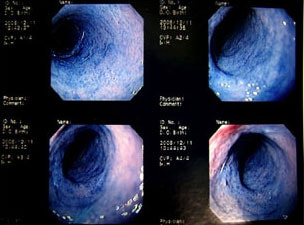

11歳 ミニチュア・ダックス 去勢オス

主訴:焼き鳥の竹串を食べたとの事で来院しました。元気・食欲は問題なく、嘔吐などの症状もありませんでした。便にも竹串が1/3程でているとの事でしたが、全ての竹串が出ていないため、内視鏡検査を実施致しました。

内視鏡検査所見:胃内に竹串の先端部分が残っていたため、異物鉗子にて摘出しました。胃内は、全体的に炎症を伴い、出血している部位も確認されました。摘出後は、胃粘膜保護薬・プロトンプインヒビター(胃薬)の内服2剤ならびに食事療法により経過は良好です。

内視鏡下写真